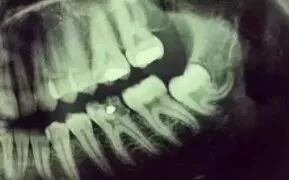

拍一张根尖片(小牙片)的辐射剂量等于一次吃下10根香蕉

拍一张小牙片=吃10根香蕉